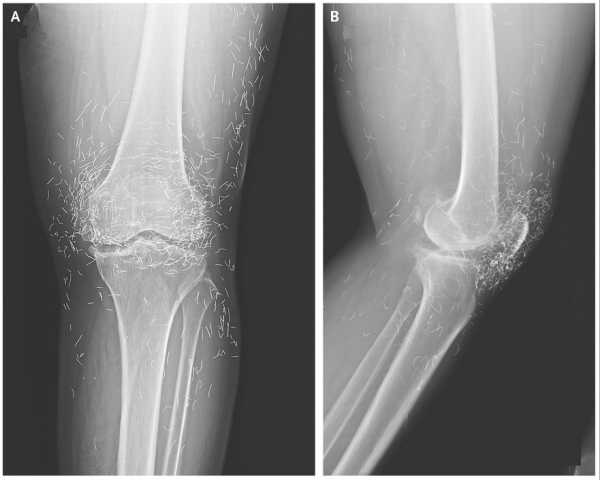

Сильний біль у коліні жінки виявив «золоті нитки» в її суглобах